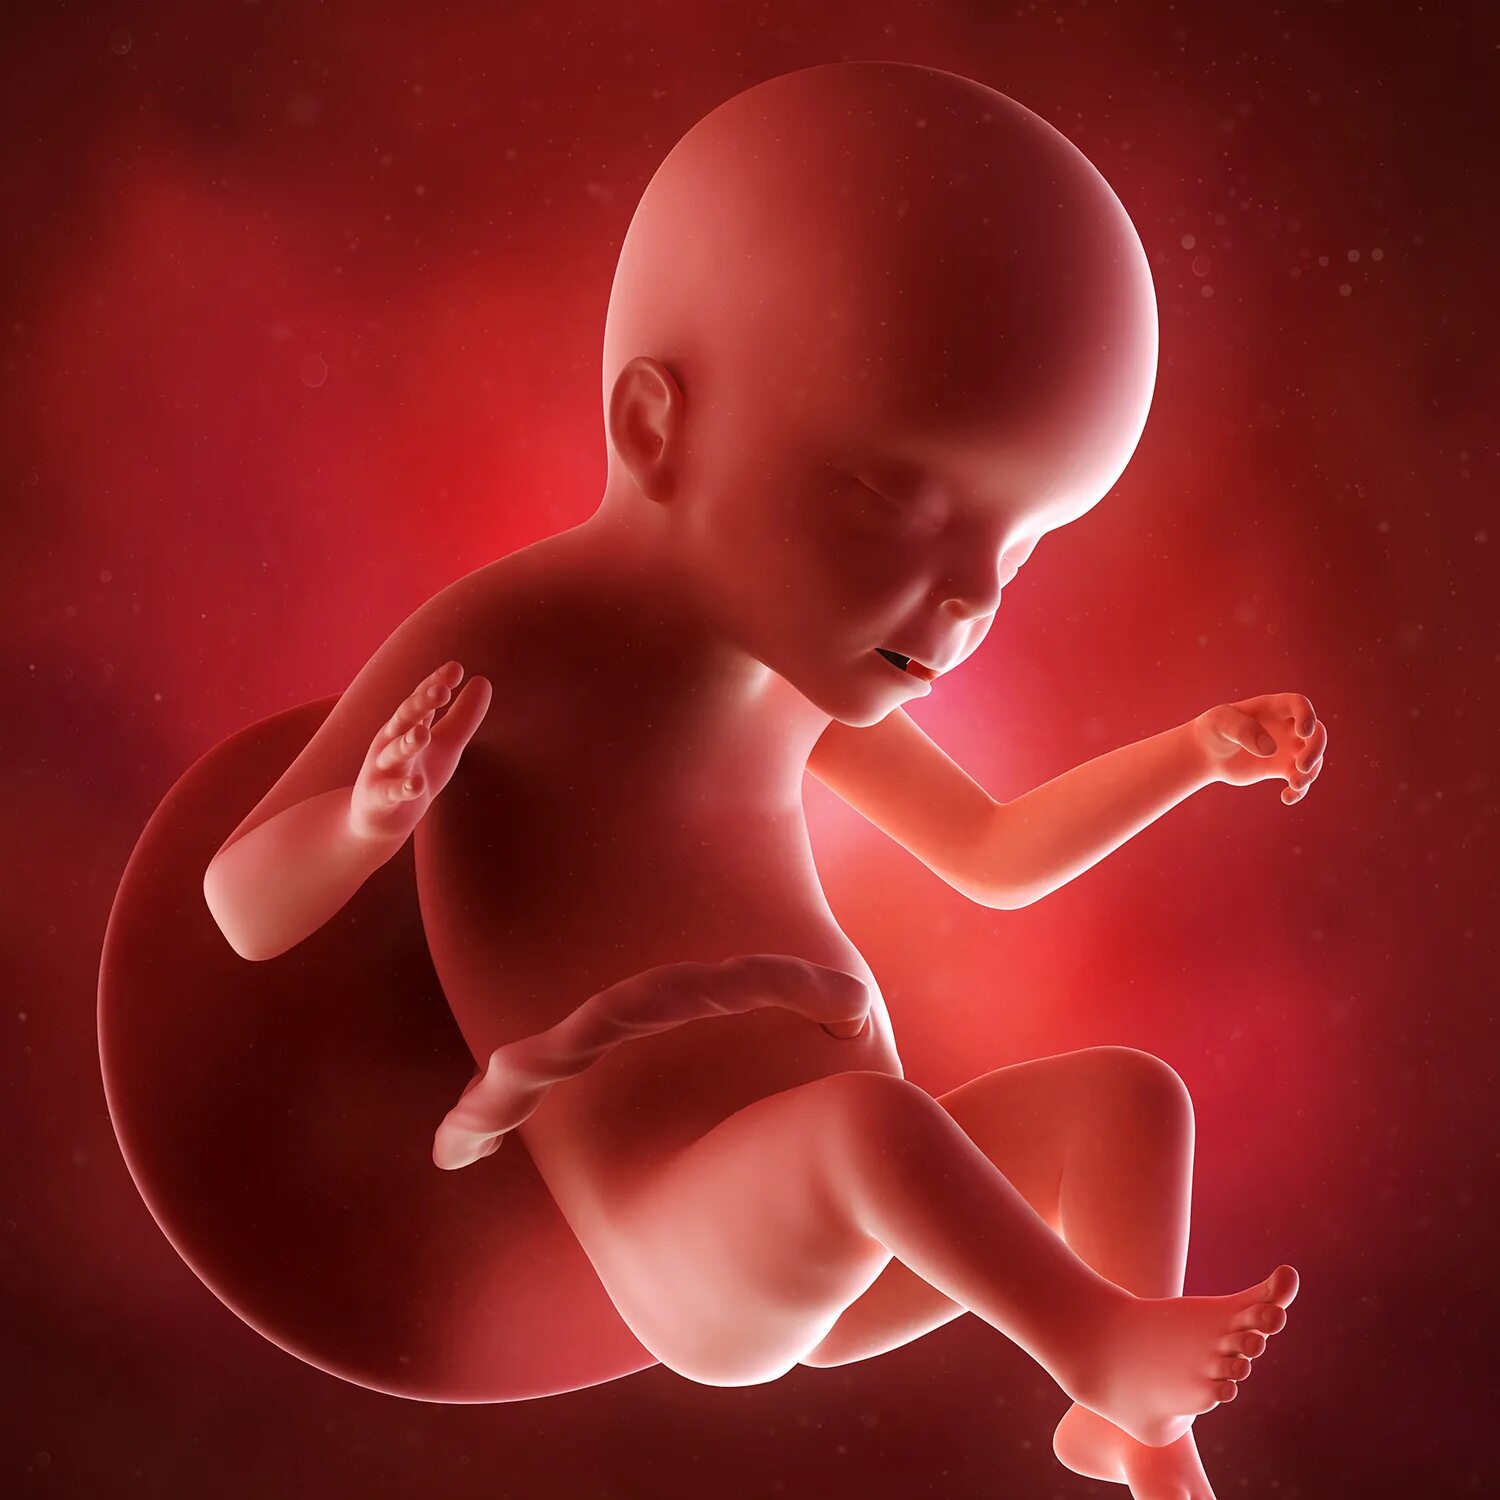

Ребенок в животе 22 недели